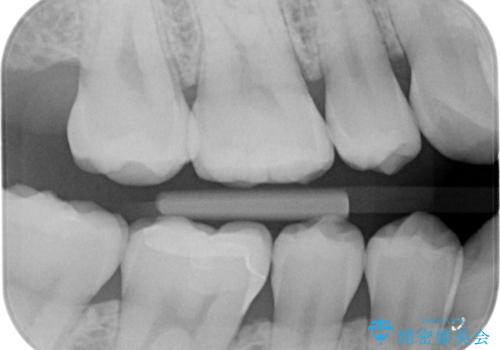

- 右下の保険治療での樹脂の劣化、および歯と歯の間の虫歯をセラミックのつめもので治療しました。

右下6番はセラミックのアンレーが入っていましたが、強度の問題もあり、やり直し後はクラウンとしました。